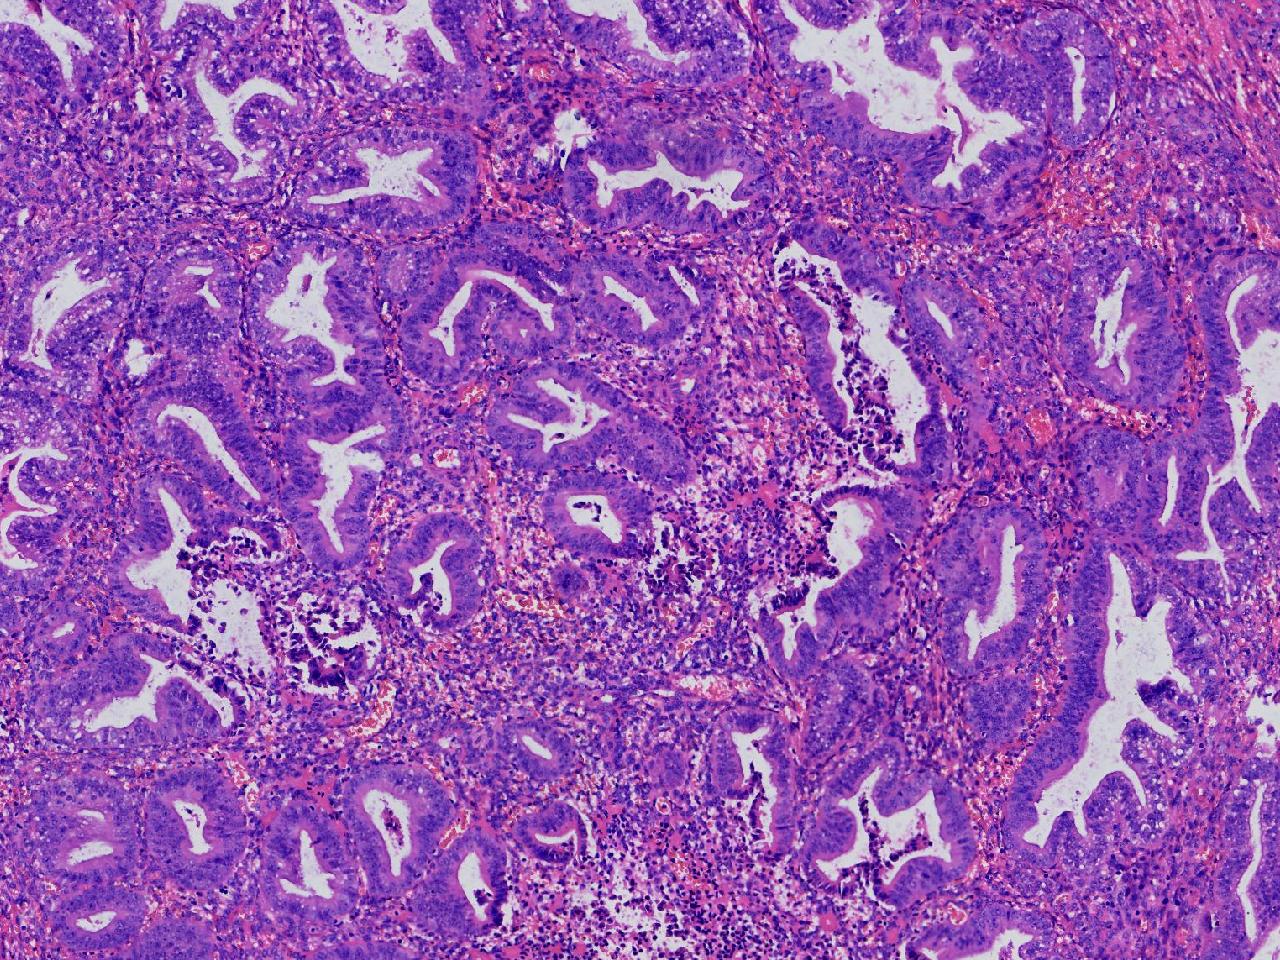

请教。1.有没有非典? 2.内膜是什么变化?

女,50岁,彩超示:粘膜厚度1.1cm。宫腔可见数个高回声,提示宫腔息肉。

子宫内膜+内膜息肉

灰粉色不整形软组织多块,3X3X2厘米。

子宫内膜息肉。

没有非典。

无非典型性子宫内膜增生,子宫内膜息肉

无非典内膜伴息肉。